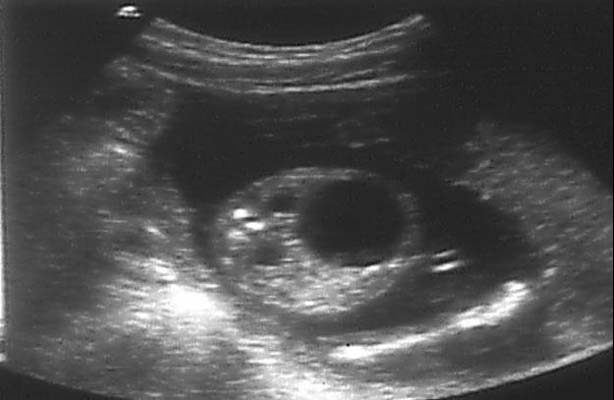

Si atteinte bilatérale ou unilatérale sur rein unique, apprécier :

- La quantité de liquide amniotique